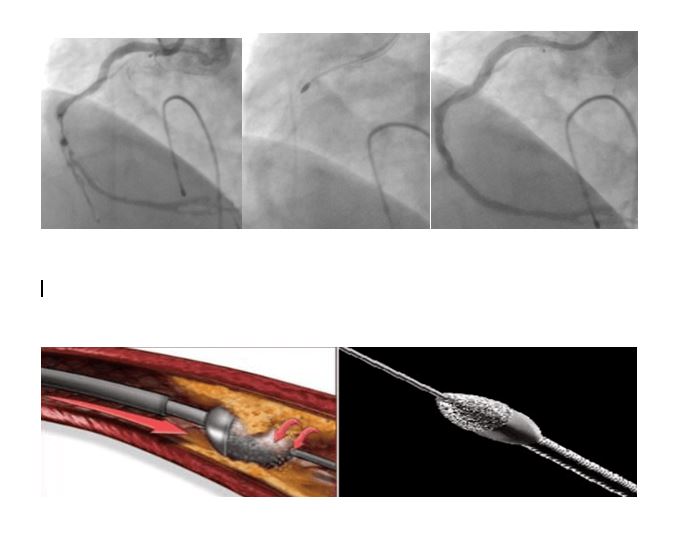

“Kalp damar hastalığı, koroner arter denilen, kalbi besleyen damarların tıkanması sebebiyle olmaktadır. Bu tıkanmaların en sık görülen sebebi ise ateroskleroz olarak adlandırılan damar duvarında yağlı plakların birikip zaman içerisinde damar boşluğuna doğru ilerleyip damar içinde kan akışını engellemesidir. Yağlı plaklar bazen kireçlenerek daha katı ve sert plaklar oluşturmaktadır. Bu kireçlenmiş plaklar ise bazen tıkanıklığı açmakta kullanılan balon/stent gibi malzemelerin geçişini engellemekte ve imkânsız kılmaktadır. Sonuçta balon/stent damar tıkanıklığı içerisinden geçemediği için tıkanıklık açılamamaktadır. Ek olarak, uygun olmayan malzemelerin kullanılması ile damarda yırtılma ve delinme gibi sorunlara yol açarak hastanın hayatını tehlikeye atan durumlar ortaya çıkmaktadır.Bu sert plakların açılmasında birtakım yeni teknolojiler kullanıma girmiştir. Bunlardan biri rotablatör (tıraşlama cihazı)’dür. Tıraşlama yöntemi ile damarı tıkayan kireçli plak yapısı parçalanarak darlıklar açılmakta, arkasından da balon/stent işlemi yapılmaktadır. Bu teknolojinin bir diğer faydası ise sert plaklara uygulanan stentin ileride tıkanma ihtimalini azaltmasıdır. Hastamızın sırasıyla; işlem öncesi, işlem esnasında ve işlem sonrasına ait sağ kalp damarına ait görüntüler izlenmektedir. Biz de merkezimizde ilk defa uyguladığımız bu işlemi başarı ile gerçekleştirdik ve hastamızı sağlığına kavuşturduk.”